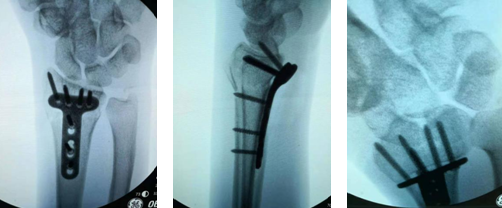

第二天上午,齐主任手术团队为大姐安排了微创手术。手术特别顺利,一个小时就完成了。齐主任在大姐的左手手腕内侧做了一个横微切口,切口仅1厘米长,并用T形钢板内固定,术后大姐安返病房。

齐主任查房的时候,问大姐术后感觉如何?只见大姐笑着给齐主任竖了一个大拇指,她说,“齐主任果然名不虚传,人家手术切口6厘米,我这只有1厘米,我感觉可好了。”